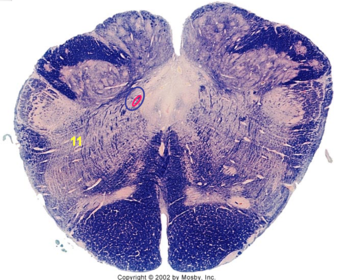

| Spinal tract of V | |

| Spinal nucleus of V | |

| Medial vestibular nucleus | |

| Inferior vestibular nucleus | |

| Dorsal cochlear nucleus | |

| Ventral cochlear nucleus | |

| Inferior olivary complex | |

| Inferior cerebellar peduncle | |

| CN IX | |

| Anterior spinocerebellar tract | |

| Central tegmental tract | |

| Olivary internal arcuate fibers | |

| Solitary tract | |

| Abducens root fibers | |

| Longitudinal pontine fibers (corticospinal tract) | |

| Transverse pontine fibers (dark fibers) | |

| Pontine nuclei (pale) | |

| Medial lemniscus | |

| ALS | |

| Trapezoid body | |

| Ventral trigeminothalamic tract | |

| Superior olive | |

| Facial nerve root fibers - descending | |

| Facial motor nucleus | |

| Interposed nuclei | |

| Medial longitudinal fasciculus | |

| Facial nerve root - internal genu | |

| Abducens nucleus | |

| Lateral vestibular nucleus | |

| Superior vestibular nucleus | |

| Superior cerebellar peduncle | |

| Dentate nucleus | |

| Fastigial nucleus | |